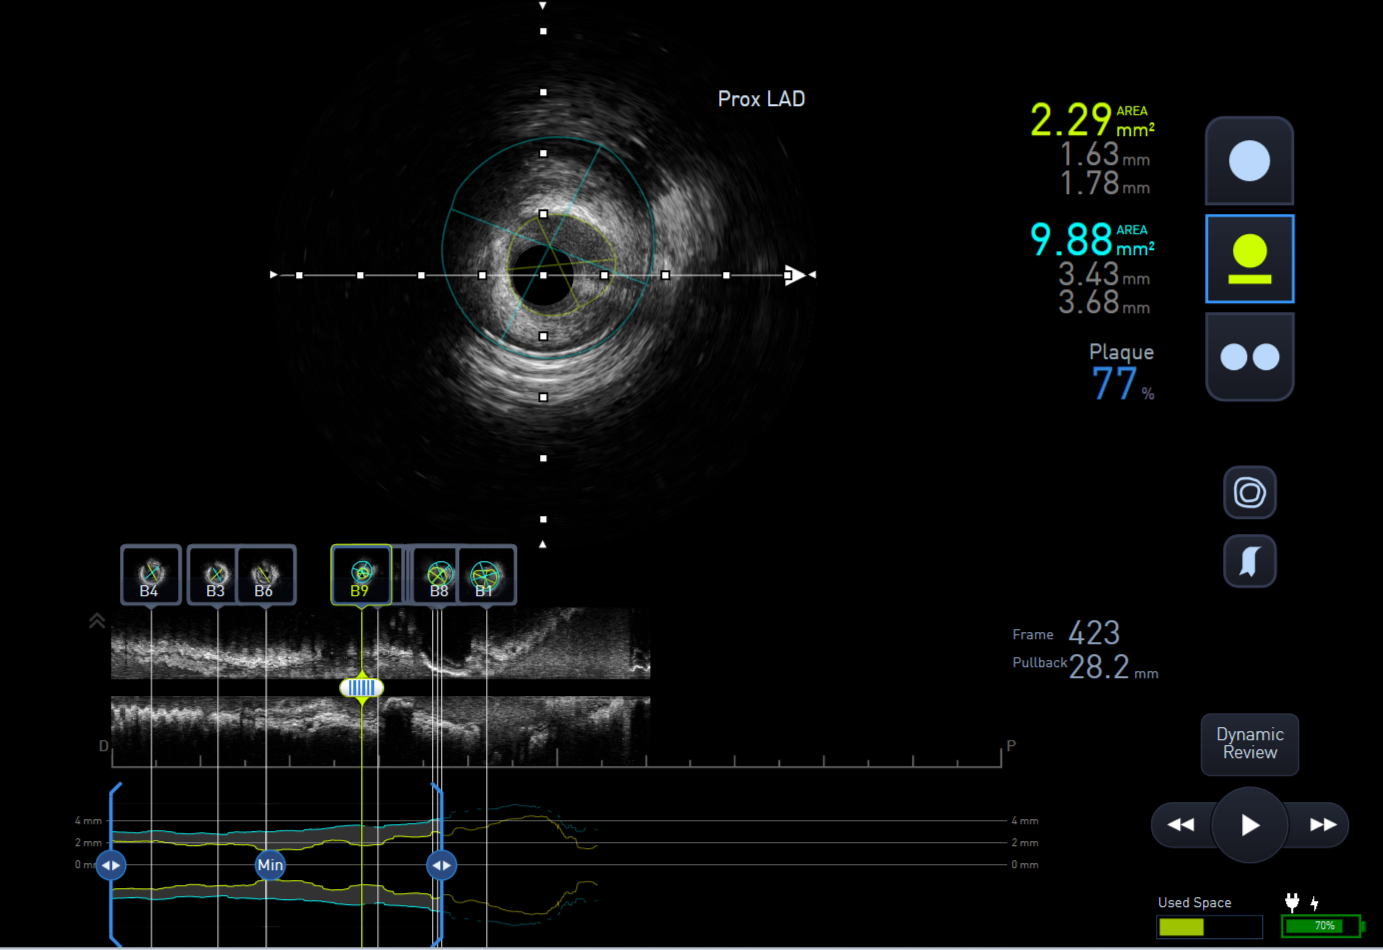

The lesion was predilated with a 2.0x15mm semi-compliant balloon to facilitate IVUS passing through the lesion. IVUS assessment showed distal Left main stem minimal lumen area (MLA) of 10mm2, proximal LAD 3.5mm2 and mid LAD 2.75mm2.